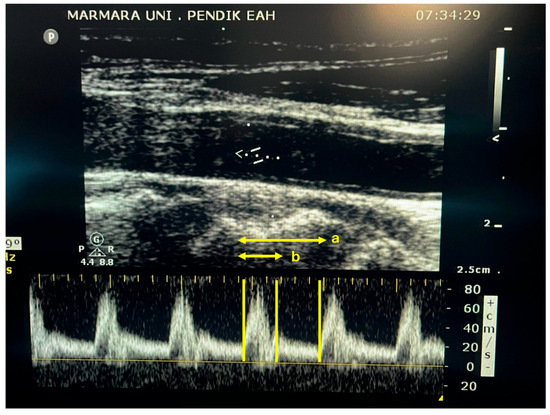

3.5. Carotid Ultrasonography

Figure 1.

Carotid Doppler ultrasound image, showing a pulsed-wave Doppler signal. a: total cycle time; b: systolic flow time.